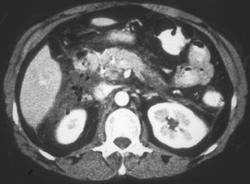

Islet Cell Carcinoma of the Pancreas in 3D Angiography